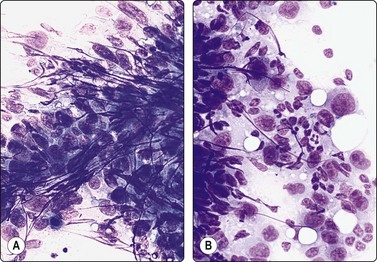

image image

Fig. 5.5 Reactive lymphadenopathy, follicular

Smear derived from reactive follicle. Centroblasts, centrocytes, small lymphocytes and tingible body macrophages with nuclear fragments (A, MGG; B, Pap; HP).